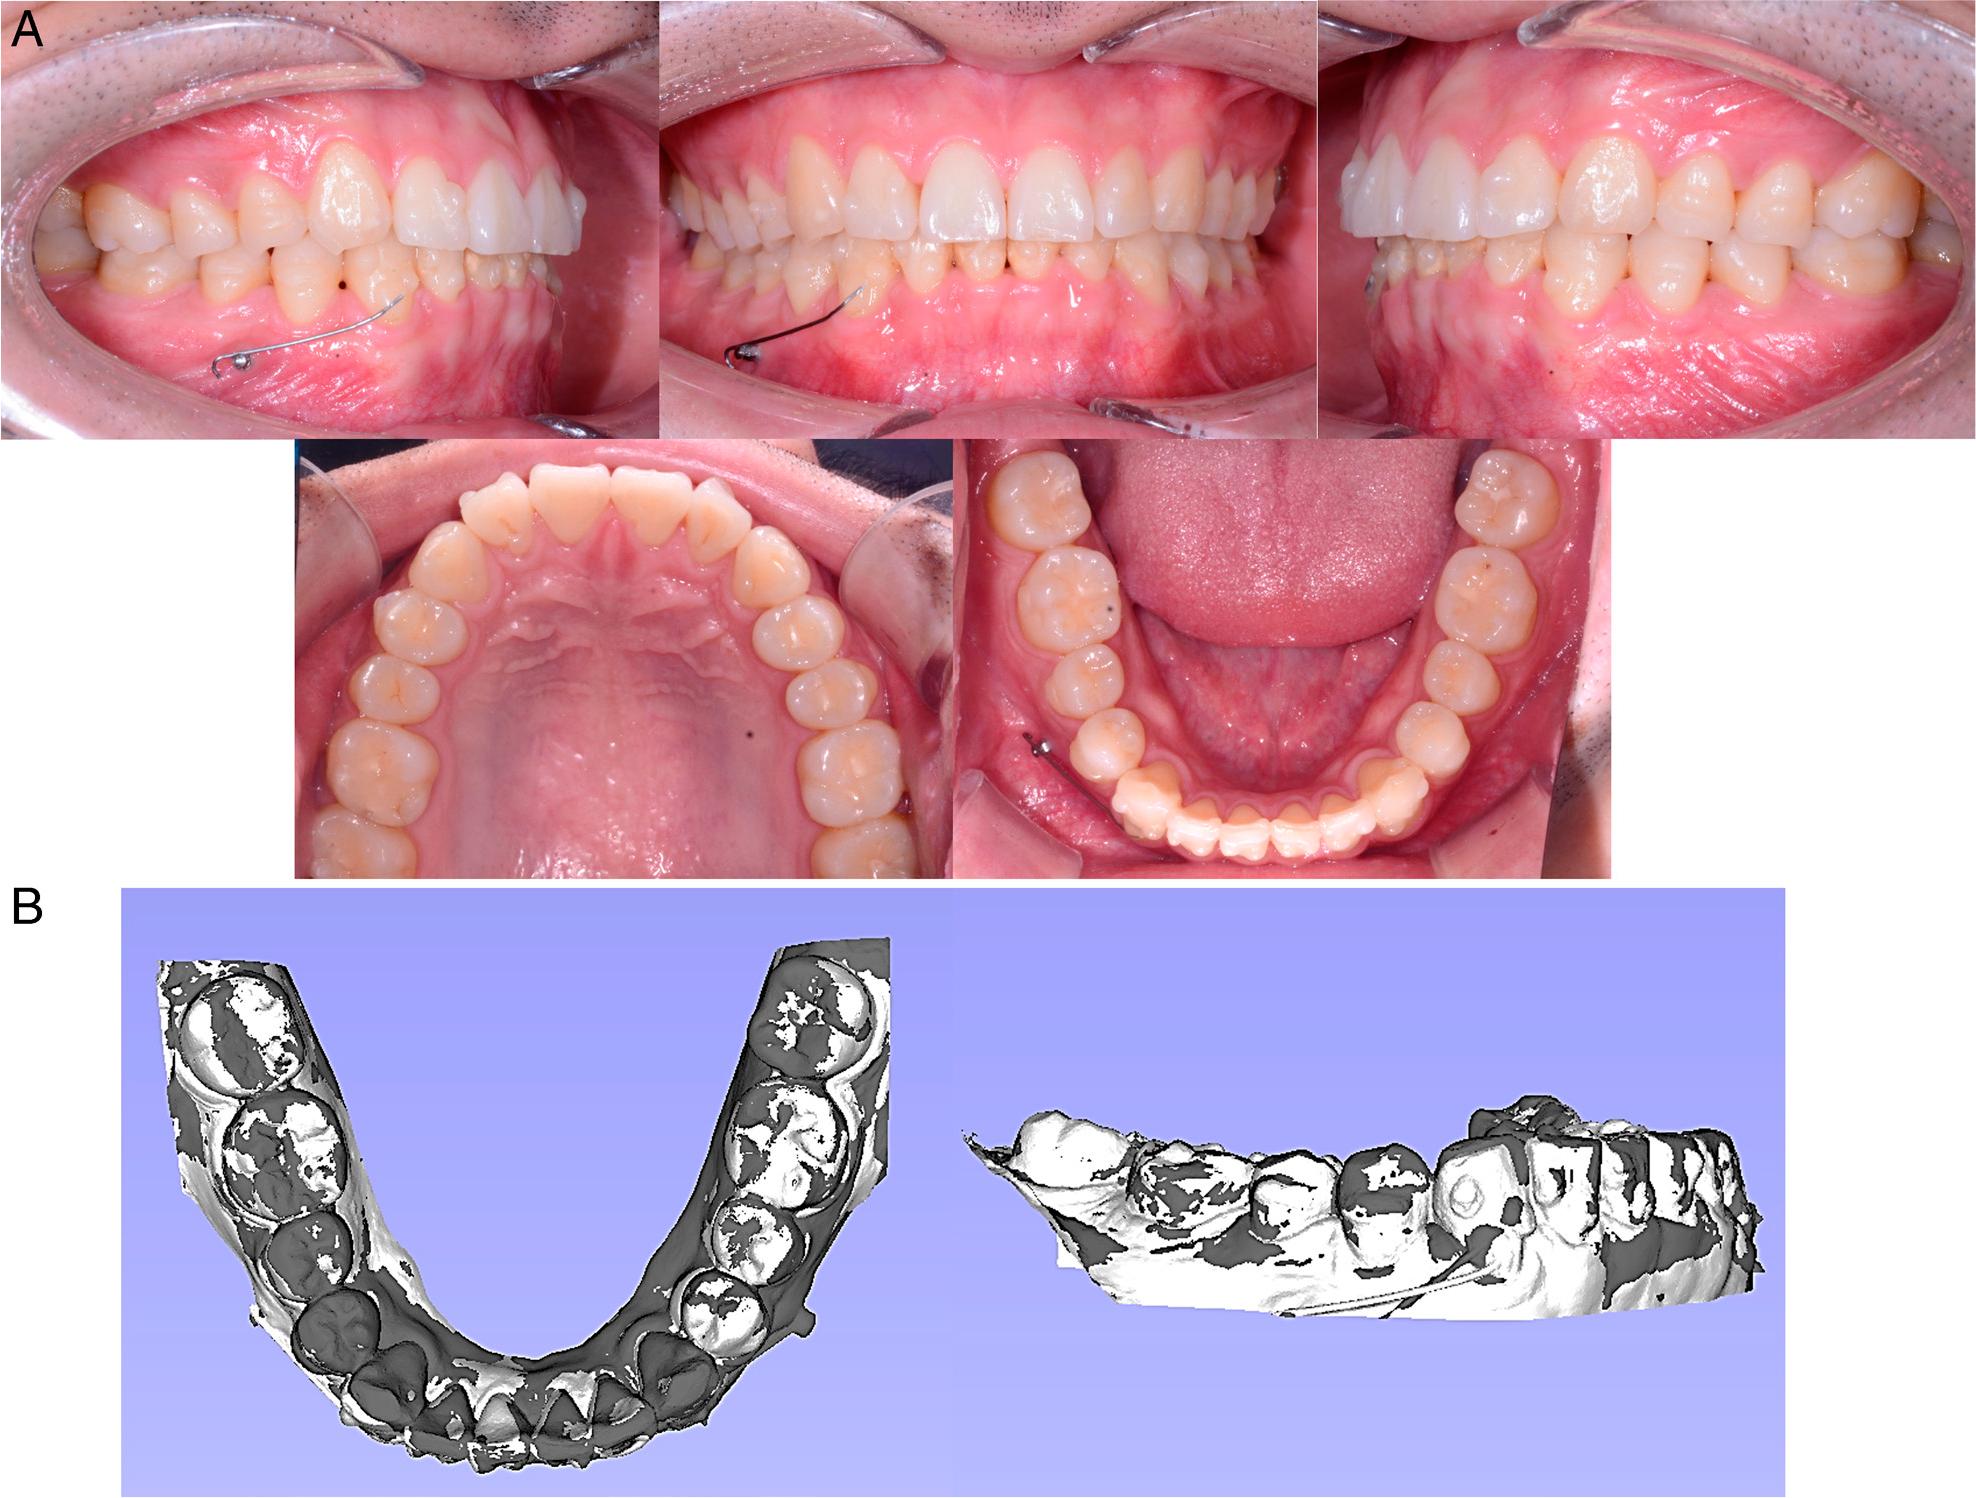

After 15.5 months of treatment, a notable change was observed in the position of the right mandibular canine (Figure 7) but it still required further correction. In addition, the mandibular incisors exhibited mild rotation. Moreover, a mild distal angulation of the left mandibular canine was also identified. Accordingly, a new set of aligners was applied with an additional micro-implant-supported NiTi cantilever. This new auxiliary wire aimed to correct the distal angulation by root uprighting (Figure 8). A total of seven sets of aligners were fabricated and worn for 2.5 months.

Treatment progress at 15.5 months. A, Intraoral photographs. B, Model superimposition. The white colour denotes the model at 12.5 months, and the dark colour represents the 15.5-month stage. The registrations were performed on the occlusal surfaces of the first and second molars.